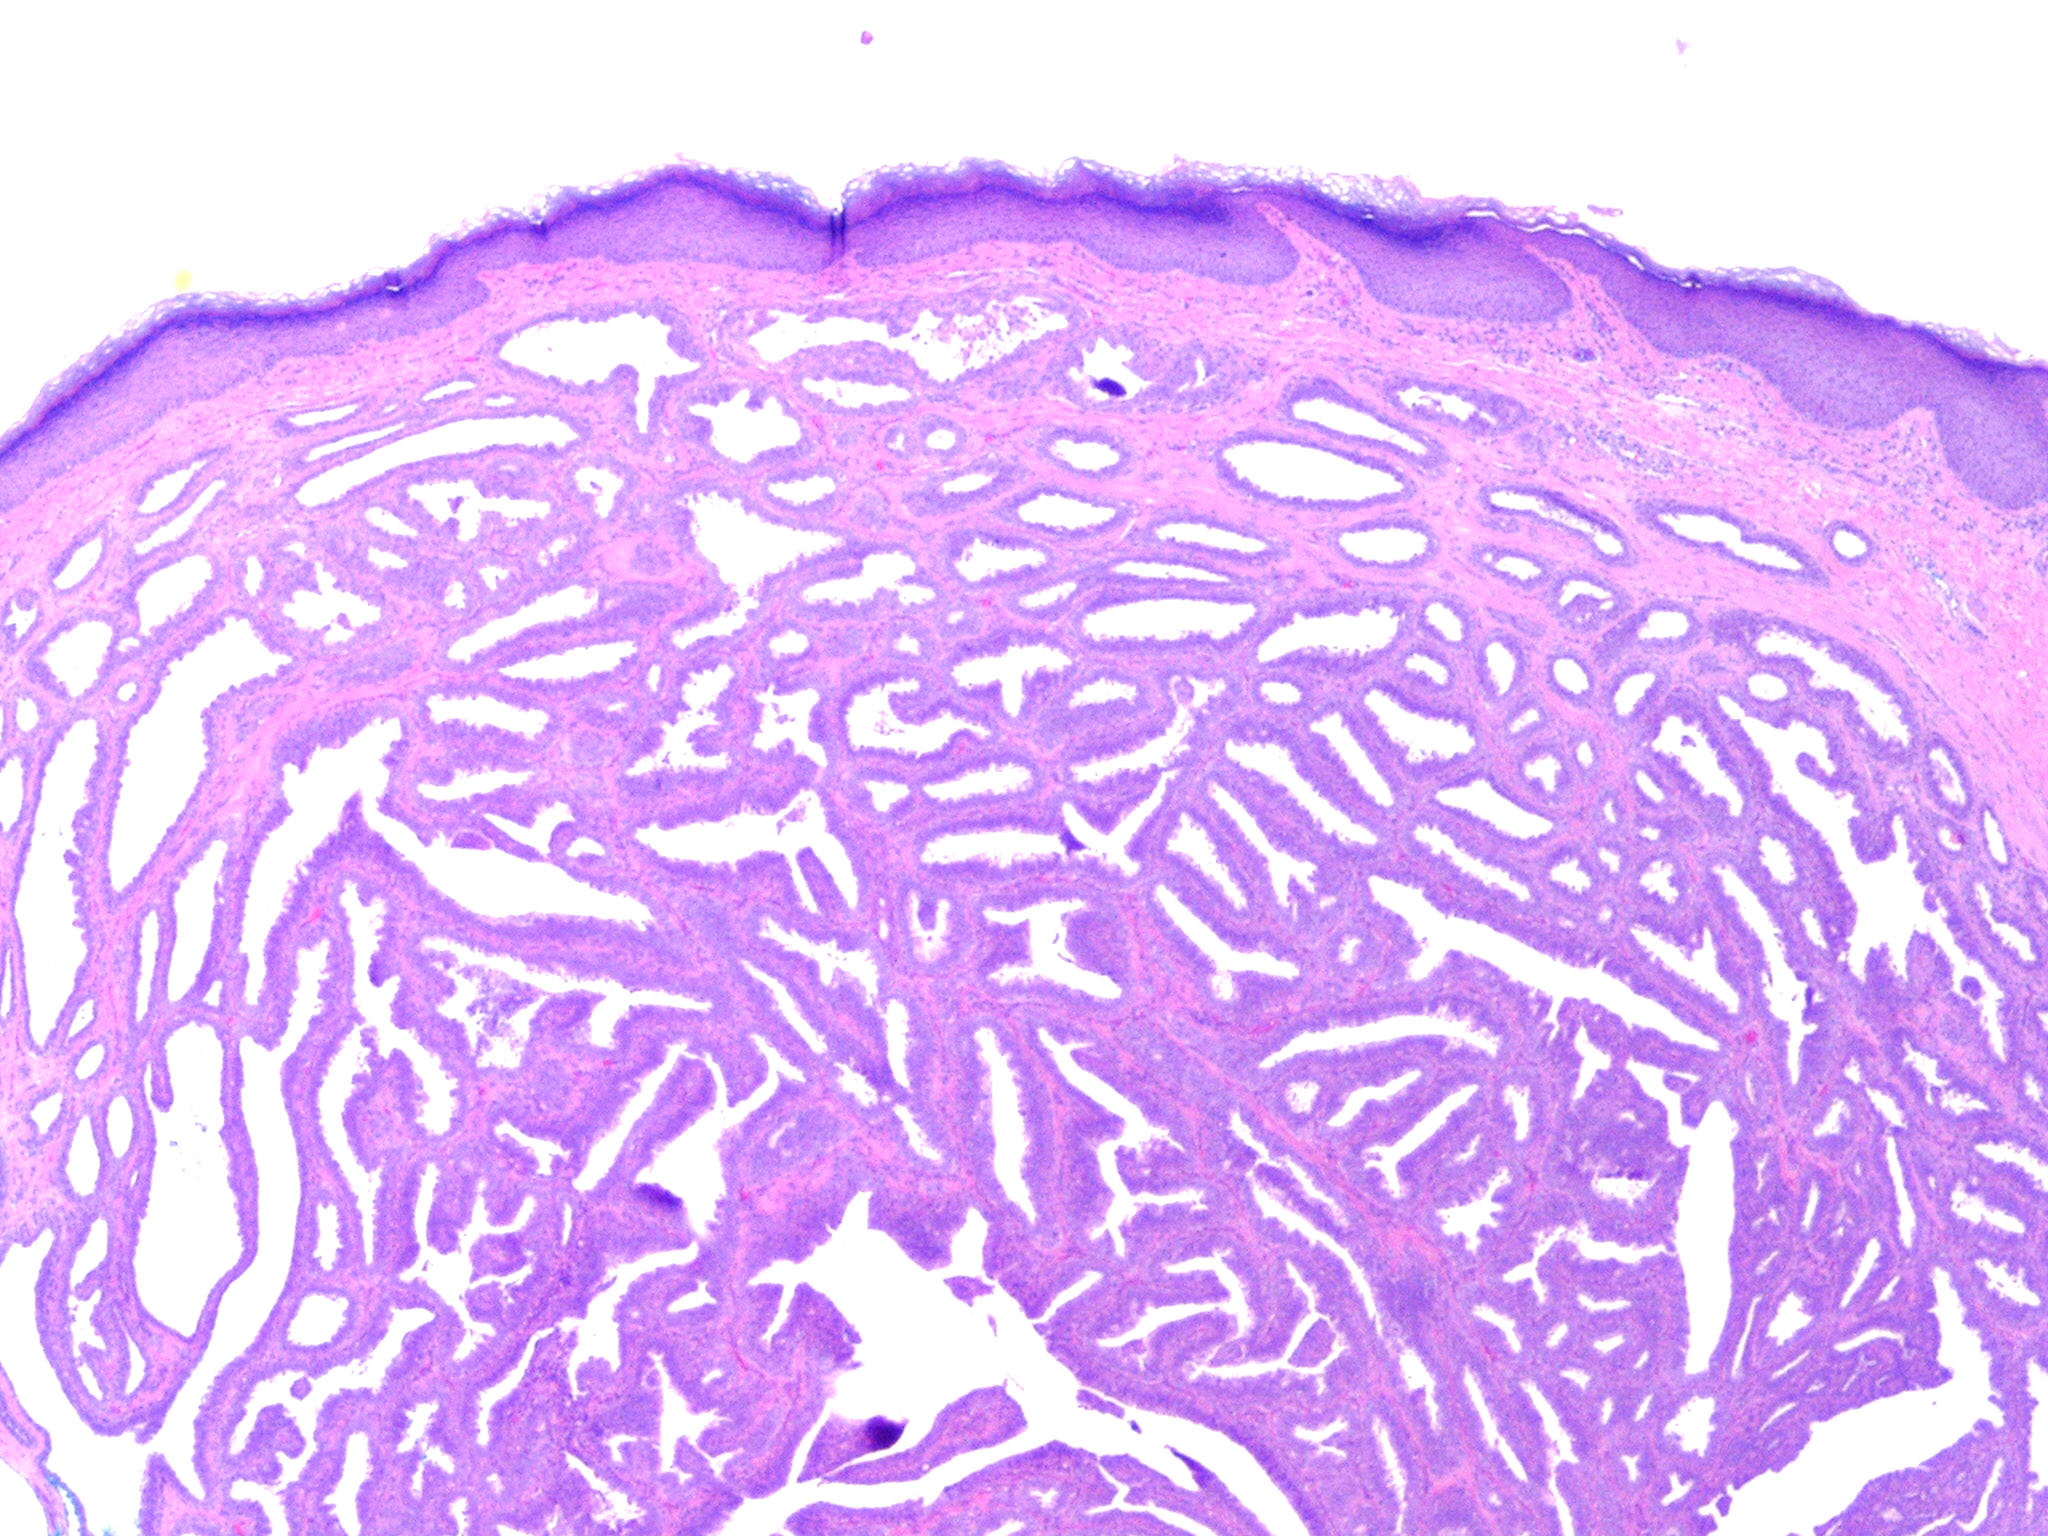

Nipple duct adenoma = غدووم في قناة الحلمة